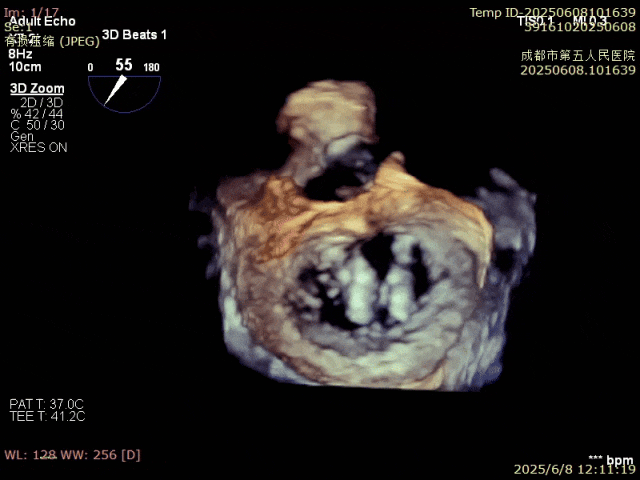

術(shù)前超聲

VFMR,反流2區(qū),新分型CCA型,MR重度(VC:3*14mm),A2:21mm,P2:10-11mm,AP:30mm,前后葉間3mm gap,MVA約5.1cm²